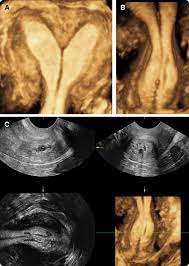

Pelvic Ultrasound In The Nongravid Patient Radiology Key

Pelvic Ultrasound In The Nongravid Patient Radiology Key from radiologykey.com